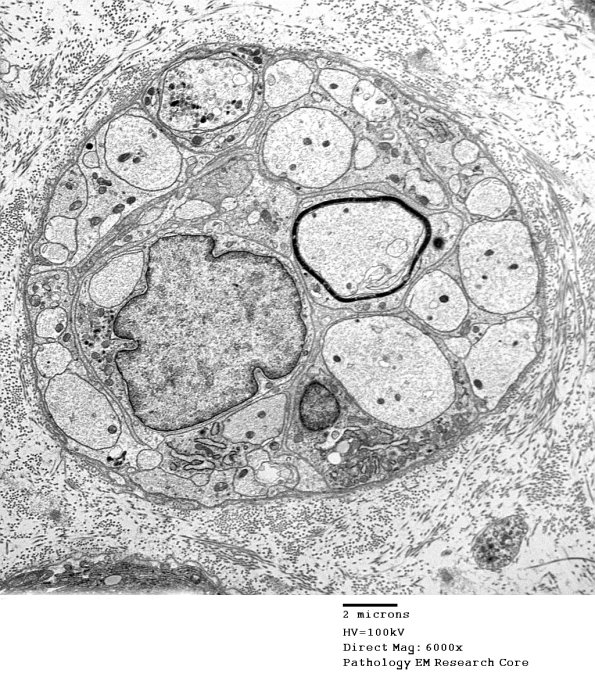

This collection of axons is between a regenerative cluster and a mini-fascicle but a clear trauma-produced structure in any case. (Electron micrograph)